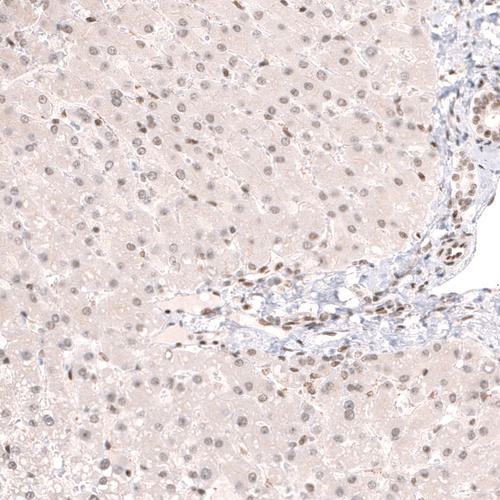

Immunohistochemistry analysis in human testis and liver tissues using HPA044341 antibody. Corresponding CIC RNA-seq data are presented for the same tissues.